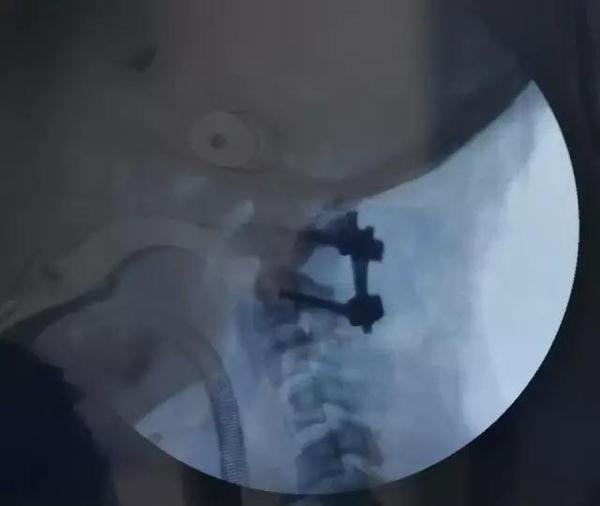

术后影像资料

2、术后复查见复位满意,脊髓减压充分,颈脊角纠正满意。

4、采用Goel技术治疗寰枢椎脱位,短节段固定融合,枕颈活动丢失较小,术后发生断钉断棒风险小,在一定程度上优于枕颈融合复位固定手术。